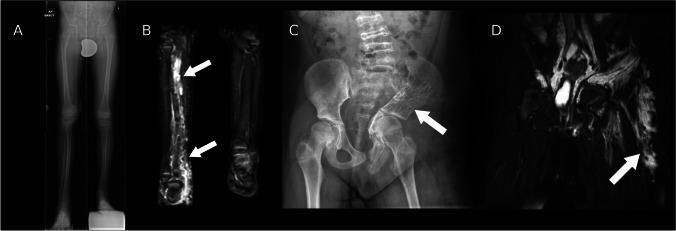

Somatic overgrowth disorders comprise a wide range of rare conditions that present with focal enlargement of one or more tissue types. The PI3K-AKT-mTOR pathway is a signalling pathway that induces angiogenesis and cell proliferation, and is one of the most commonly overactivated signalling pathways in cancer. The PI3K-AKT-mTOR pathway can be up-regulated by genetic variants that code for proteins in this pathway, or down-regulated by proteins that inhibit the pathway. Mosaic genetic variations can result in cells that proliferate excessively in specific anatomical locations. The PIK3CA-related overgrowth spectrum (PROS) disorders include CLOVES syndrome, macrodystrophia lipomatosa, and Klippel-Trenaunay syndrome among many. The neurofibromatosis type 1 (NF1) gene encodes neurofibromin which down-regulates the PI3K-AKT-mTOR pathway. Thousands of pathological variants in the NF1 gene have been described which can result in lower-than-normal levels of neurofibromin and therefore up-regulation of the PI3K-AKT-mTOR pathway promoting cellular overgrowth. Somatic overgrowth is a rare presentation in NF1 with a wide range of clinical and radiological presentations. Hypertrophy of all ectodermal and mesodermal elements has been described in NF1 including bone, muscle, fat, nerve, lymphatics, arteries and veins, and skin. The shared signalling pathway for cellular overgrowth means that these radiological appearances can overlap with other conditions in the PIK3CA-related overgrowth spectrum. The aim of this review is to describe the genetic basis for the radiological features of NF1 and in particular compare the appearances of the somatic overgrowth disorders in NF1 with other conditions in the PIK3CA-related overgrowth spectrum.